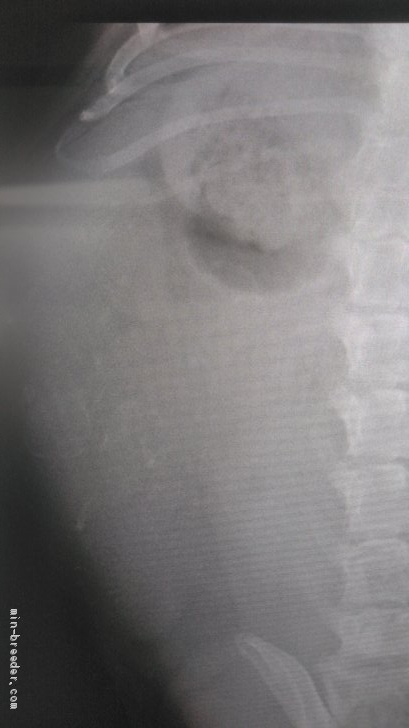

出産予定日まで4日🤭何頭かなぁ〜?出産予定日まで4日‼︎ てんちゃんレントゲン🩻撮影しました❣️ 5頭かなぁ〜? ...

レントゲン撮影をしました🐶🐶🐶🐶…出産予定日まで11日☺️❣️ 本日、頭数確認のためレントゲン写真を撮ったのですが、あ...

お腹の子犬は3頭‥?4頭‥?5頭‥?6頭‥?笑😁♥️本日はエコー検査とレントゲン検査😊💓 元気元気〜 子犬わかますかー? お腹の...